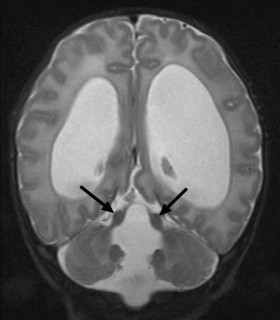

Joubert综合症是一种遗传疾病,影响小脑和脑干的发育,这些大脑区域协调动作、调节呼吸、吞咽、心率和意识等基础功能。这一最新研究证实了导致JS和cillia细胞结构遗传变化的关键信息。

Jourbert综合症患者因小脑蚓部(cerebellar vermis)和脑干部分发育不良或畸形,而有程度不一的病症出现:包括缺乏肌肉控制力、呼吸过强(hypernea)、眼睛和舌头运动异常、和肾脏方面等问题。病症的严重程度不一可能因基因修饰者的存在而影响疾病严重和表现程度。此疾病相当罕见,病患数量少不易进行基因分析,因此相关基因研究相当缓慢。